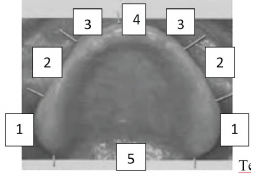

Observe a imagem a seguir das regiões do rebordo superior:

Está correta a correspondência da delimitação funcional para base da prótese superior na seguinte alternativa: